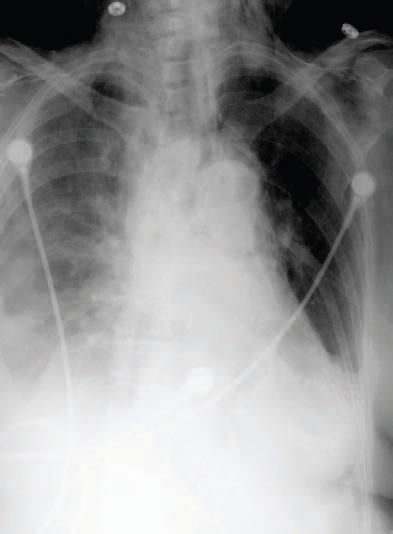

Postoperatively, the patient was stable, although she complained of a sore throat and hoarseness. The physical examination findings were remarkable for crepitations in the neck and supraclavicular fossae. On the first postoperative day (November 5), the chest radiograph revealed subcutaneous air in the neck and a pneumomediastinum that persisted the following day (Figure 1). The patient had a history of penicillin allergy. The empirical antibiotic coverage was switched from levofloxacin and metronidazole to cefotaxime and clindamycin.

Figure 1 - A chest radiographobtained November 5, 2005,shows subcutaneous emphysemain the left side of the neck andsuggestion of pneumomediastinum.The diameter of thesuperior mediastinum iswithin normal limits.Bilateral pulmonaryinfiltrates are greaterin the right lungthan in the left lung.